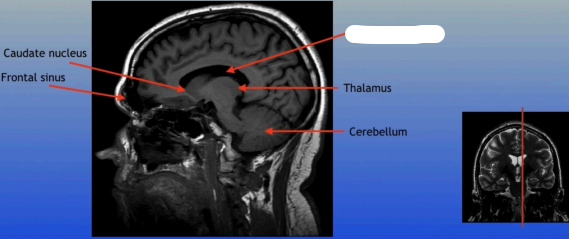

Caudate Nucleus

A C-shaped structure within the brain's basal ganglia, involved in various functions including motor control and learning.

Frontal Sinus

A paired cavity located within the frontal bone, above the eyes, that plays a role in sinus drainage and resonance of the voice.

Thalamus

A large mass of gray matter located in the diencephalon, acting as a relay station for sensory information and playing a key role in regulating consciousness and sleep.

Cerebellum

A large structure located at the back of the brain responsible for coordination, balance, and fine motor control.